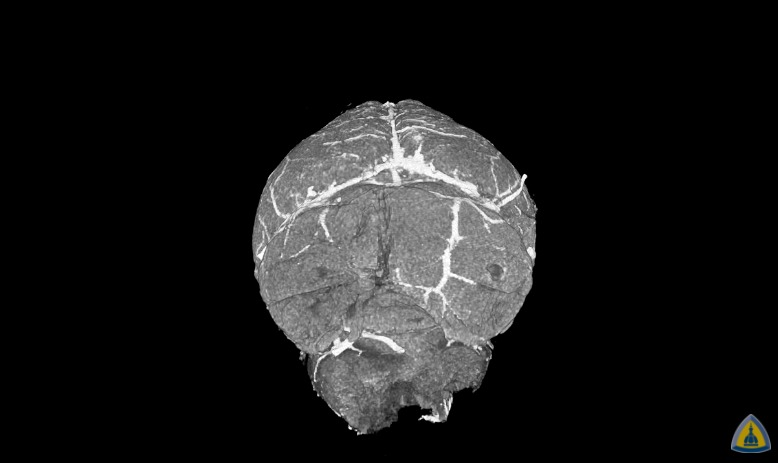

Johns Hopkins Medicine researchers have developed and tested a new imaging approach they say will accelerate imaging-based research in the lab by allowing investigators to capture images of blood vessels at different spatial scales according to a new report.

The method, dubbed “VascuViz,” includes a quick-setting polymer mixture to fill blood vessels and make them visible in multiple imaging techniques. The approach enables researchers to visualize the structure of a tissue’s vasculature, which in conjunction with detailed mathematical models or complementary images of other tissue elements can clarify the complex role of blood flow in health and disease, say the researchers.

The combined images of the blood vessels should not only enhance the study of the biology of diseases that involve abnormalities in blood flow, such as cancer and stroke, but also advance our understanding of the structures and functions of tissues throughout the body, they say.